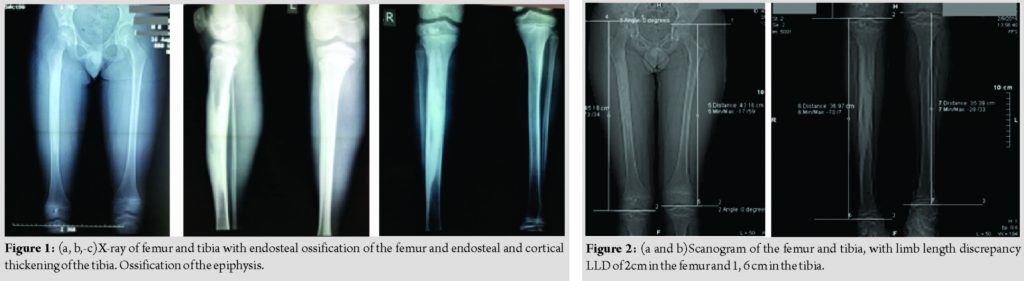

On X-ray examination of his legs, femur and tibia on the right leg had longitudinal diffuse hyperostosis, affecting the medullary canal. There was endosteal and cortical irregular thickening mainly of the tibia. There were irregular areas of ossification in the epiphysis of the femur and tibia. Endosteal ossification was present on the talus of the same foot. Growth plates were open and normal both for femur and tibia. Soft tissue was normal, with no signs of heterotopic ossification. Laboratory investigations including serum alkaline phosphatase, Ca, and P were within normal limits. We performed a scanogram that measured his discrepancy as 2 cm in the femur and 1, 6 cm in the tibia.

Melorheostosis is a rare bone dysplasia. Leg length discrepancy can be one clinical manifestation of the disease in children. Diagnosis is based on the appropriate radiographic investigation. X-ray examination and scanogram measurements are used for the monitoring of the LLD. The affected limb in our patient was the longer one. Using eight plates, we performed epiphysiodesis of the distal femur and proximal tibia and achieved almost complete equalization of the LLD.